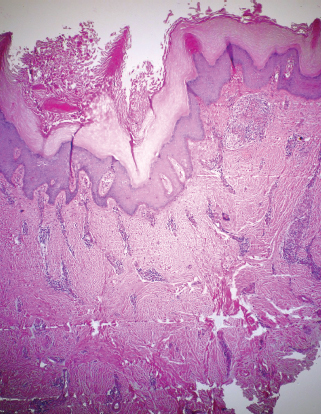

Histopathologically, the filarial tissue shows hyperproliferation of keratinocytes, focal acantholysis, an accumulation of lymphocytes at the epidermodermal junction, and profuse pericapillary and perivenular mononuclear infiltrations (Fig. 15-3).